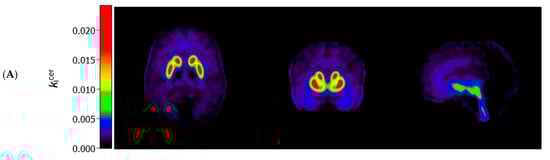

Figure 1 (panels A and B) shows the average kicer for ASD and control participants in voxels throughout the brain. In striatal as well as extrastriatal regions, we found no statistically significant differences in the kicer values between ASD and controls, and in neither sample did we observe significant associations between the kicer values and the AQ total or social interaction subscale scores. These results were similar, regardless of whether we adjusted for confounders, applied varying kicer thresholds, used unsmoothed data or data smoothed with a 4 FWHM Gaussian filter, or examined the results for the two PET/CT scanners separately. We did observe, in accordance with the ROI analysis, that kicer values in a small cluster of voxels in the left nucleus accumbens, significantly negatively correlated with the AQ attention to detail subscale in the ASD sample (and not in controls) (Figure 1C). At more lenient p-value thresholds, this association extended to larger parts of the striatum bilaterally.

Figure 1.

Axial (left), coronal (middle), and sagittal (right) view of the mean cerebral [18F]-FDOPA uptake (kicer min−1; unadjusted and unsmoothed) in (A) adults with autism spectrum disorder (n = 44) and (B) controls (n = 22). Panel (C) shows statistically significant negative associations between scores on the autism spectrum quotient attention to detail subscale and kicer values in autistic adults, overlaid on a single subject T1-weighted MRI scan, when family-wise error (FWE) rate-adjusted or unadjusted p-values of 0.05 are used (8 mm smoothing, threshold of kicer ≥ 0.005).